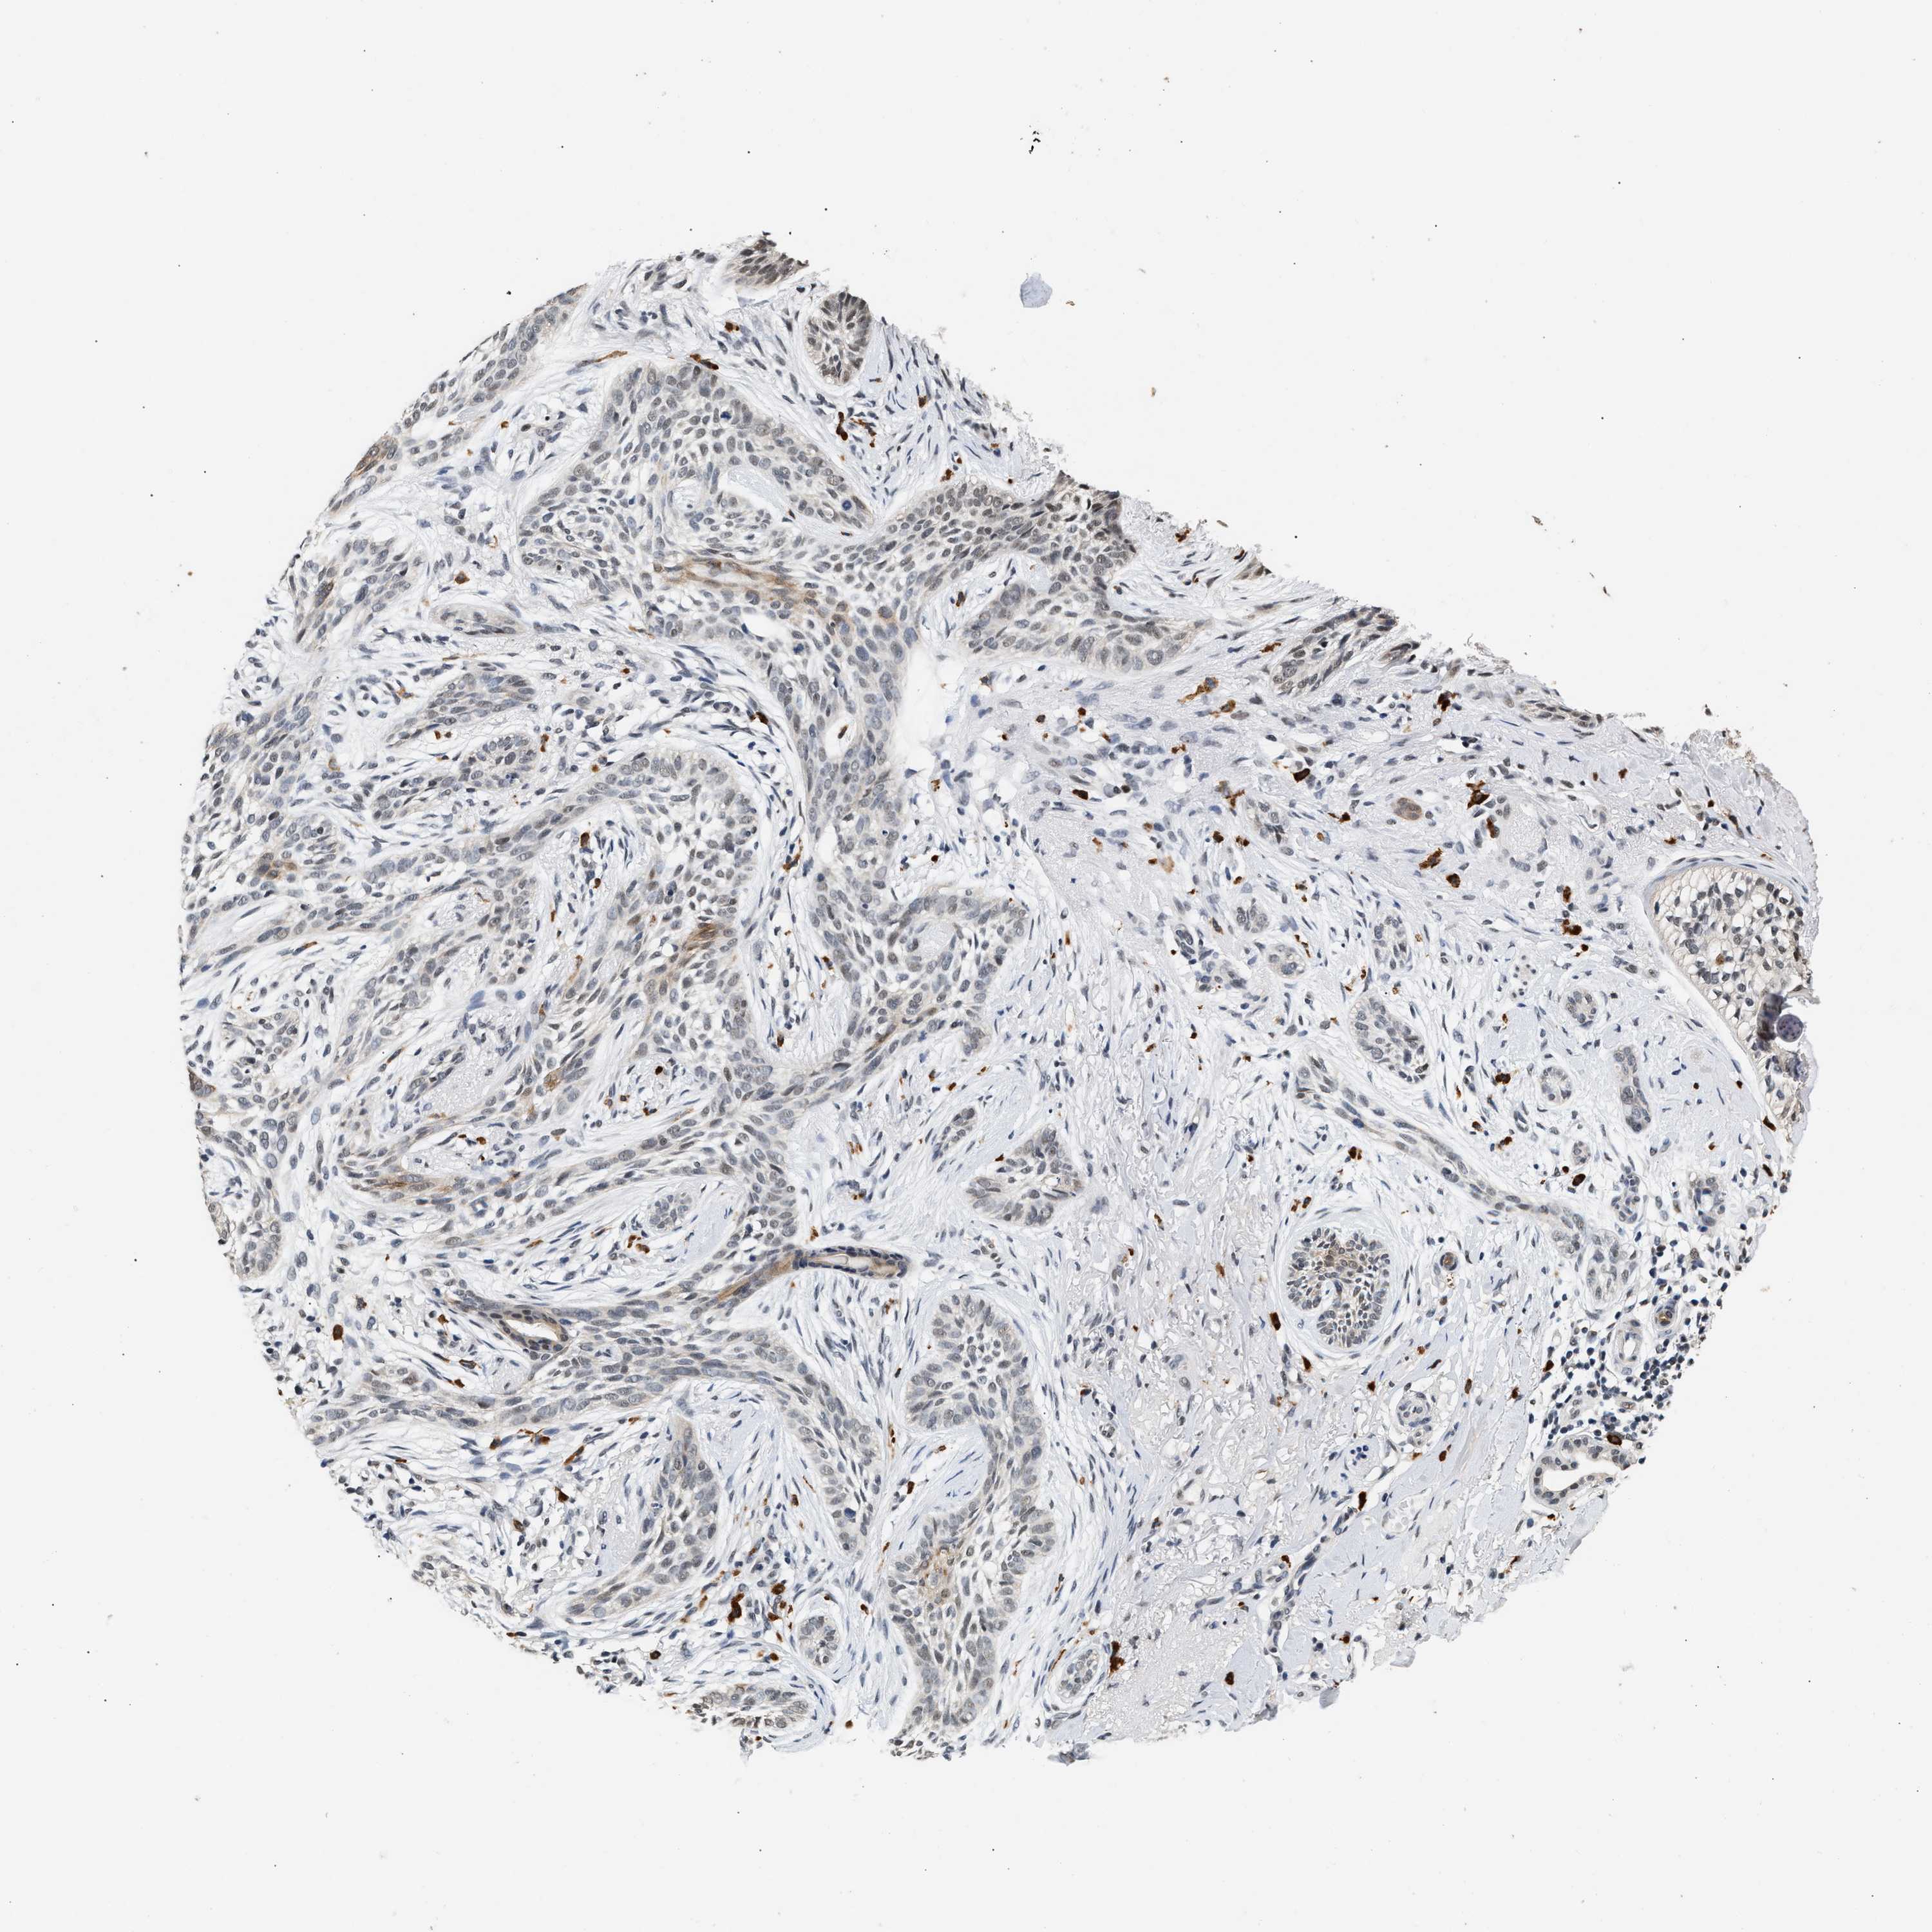

Basal cell and squamous cell cancer

SKIN CANCER - Protein expressioni

A mouse-over function shows sample information and annotation data. Click on an image to view it in a full screen mode. Samples can be filtered based on level of antibody staining by selecting one or several of the following categories: high, medium, low and not detected. The assay and annotation is described here.

Each image is clickable and will lead to virtual microscopy that enables deeper exploration of all samples and also displays staining intensity scores, fraction scores and subcellular localization as well as patient and tissue information for each sample.

Antibody HPA019096

Basal cell carcinoma

Squamous cell carcinoma, NOS